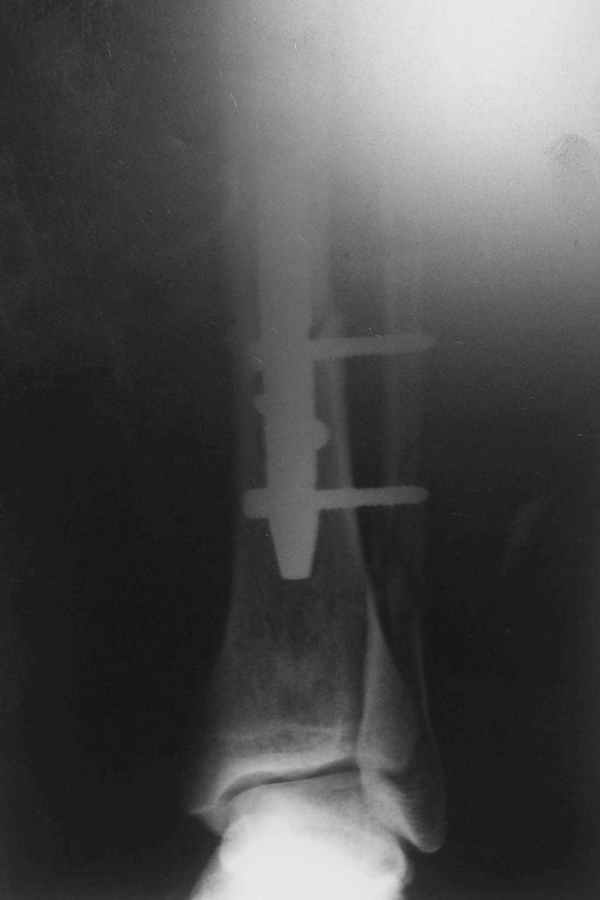

Рентгенограмы

Не удается отправить первичные снимки. А что скажите по имеющимся?!

Выполненный остосинтез нестабилен. Штифт надо заменить по "размеру" на солидный, дистльно три запирающих винта. Успехов!

Перелом спиральный, то есть низкоэнергетический, так что со сращением дело обстоит уже неплохо, лишь бы "костоеда" не развилась. Отломки выглядят уже стабилизированными костной мозолью, так что довводить винты, наверно, уже незачем. Разве что при клинической оценке подвижность еще есть - тогда можно для стабилизации наложить простейший аппарат, не опасаясь контакта его элементов с гвоздем, поскольку места в дистальном метафизе оставлено более чем достаточно.

С Александром согласен, нет необходимости делать дополнительные усилия для сращения, не большая компрессия аппаратом из двух колец и полная нагрузка доделает работу.

Потекли блокирующие винты.

Удалять их всё равно придётся.

Уже имеется какое-то сращение. А в этих условиях выполнить реостеосинтез гвоздём не дольше, чем "накинуть" аппарат из двух колец. Ходить можно сразу с полной нагрузкой, да и качество жизни пациента без аппарата лучше.